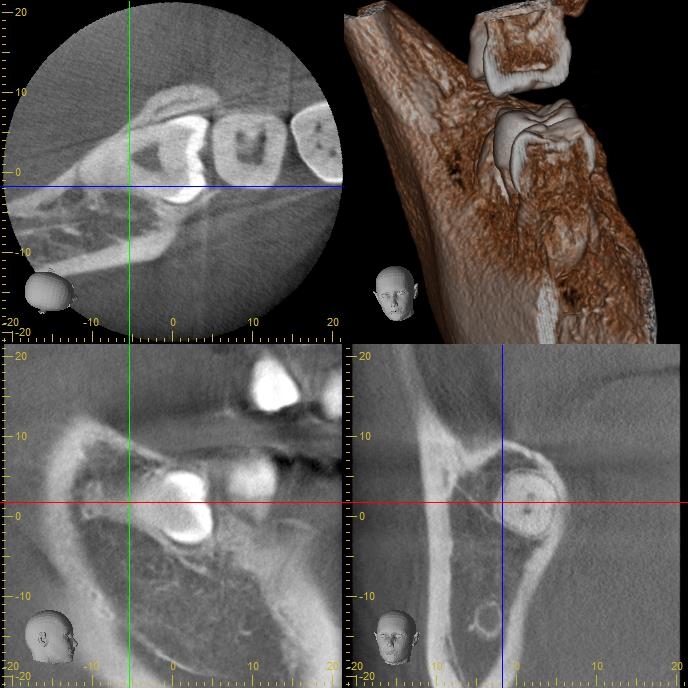

術前CT写真 (右下)

術前CT写真

CT画像で状態を確認し、親知らずの歯根の曲がり具合や歯根の太さ、

下の親知らずの場合は下歯槽管神経との距離、

位置関係や骨の厚みなどを確認します。

下歯槽神経を傷をつけないように注意が必要です。

この場合、神経との距離を測り慎重に抜歯しないといけません。